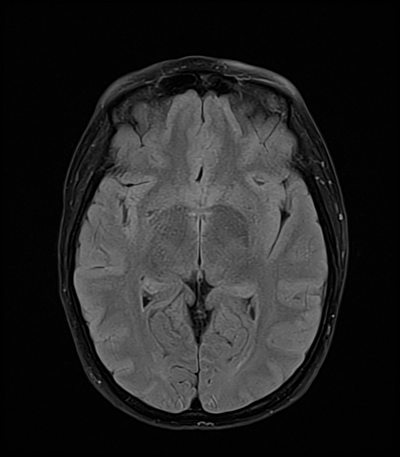

An 50 year-old man with lung adenoCA (known metastases to brain, spine, and adrenal glands) presents to the ED with worsening right arm and leg weakness. He had just gotten a routine MRI of his brain yesterday that re-demonstrated his known right occipital and left frontal metastases, though with an increase in vasogenic edema (mainly associated with the left frontal metastasis) as compared with prior. The ED consults you because of his abnormal MRI with worsening symptoms, and to inquire whether surgical intervention is acutely warranted.

MRI brain (FLAIR)